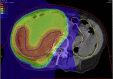

Purpose: To conduct phase 1 and 2 trials with photon intensity modulated radiation therapy and intensity modulated proton therapy (IMPT) arms to selectively escalate the retroperitoneal sarcoma preoperative radiation dose to tumor volume (clinical target volume [CTV] 2) that is judged to be at a high risk for positive margins and aim to reduce local recurrence. We report on the IMPT study arm in phase 1.

Methods and materials: Patients aged ≥18 years with primary or locally recurrent retroperitoneal sarcoma were treated with preoperative IMPT, 50.4 GyRBE in 28 fractions, to CTV1 (gross tumor volume and adjacent tissues at risk of subclinical disease) with a simultaneous integrated boost to CTV2 to doses of 60.2, 61.6, and 63.0 GyRBE in 28 fractions of 2.15, 2.20, and 2.25 GyRBE, respectively. The primary objective of the phase 1 study was to determine the maximum tolerated dose to CTV2, which will be further tested in the phase 2 study.